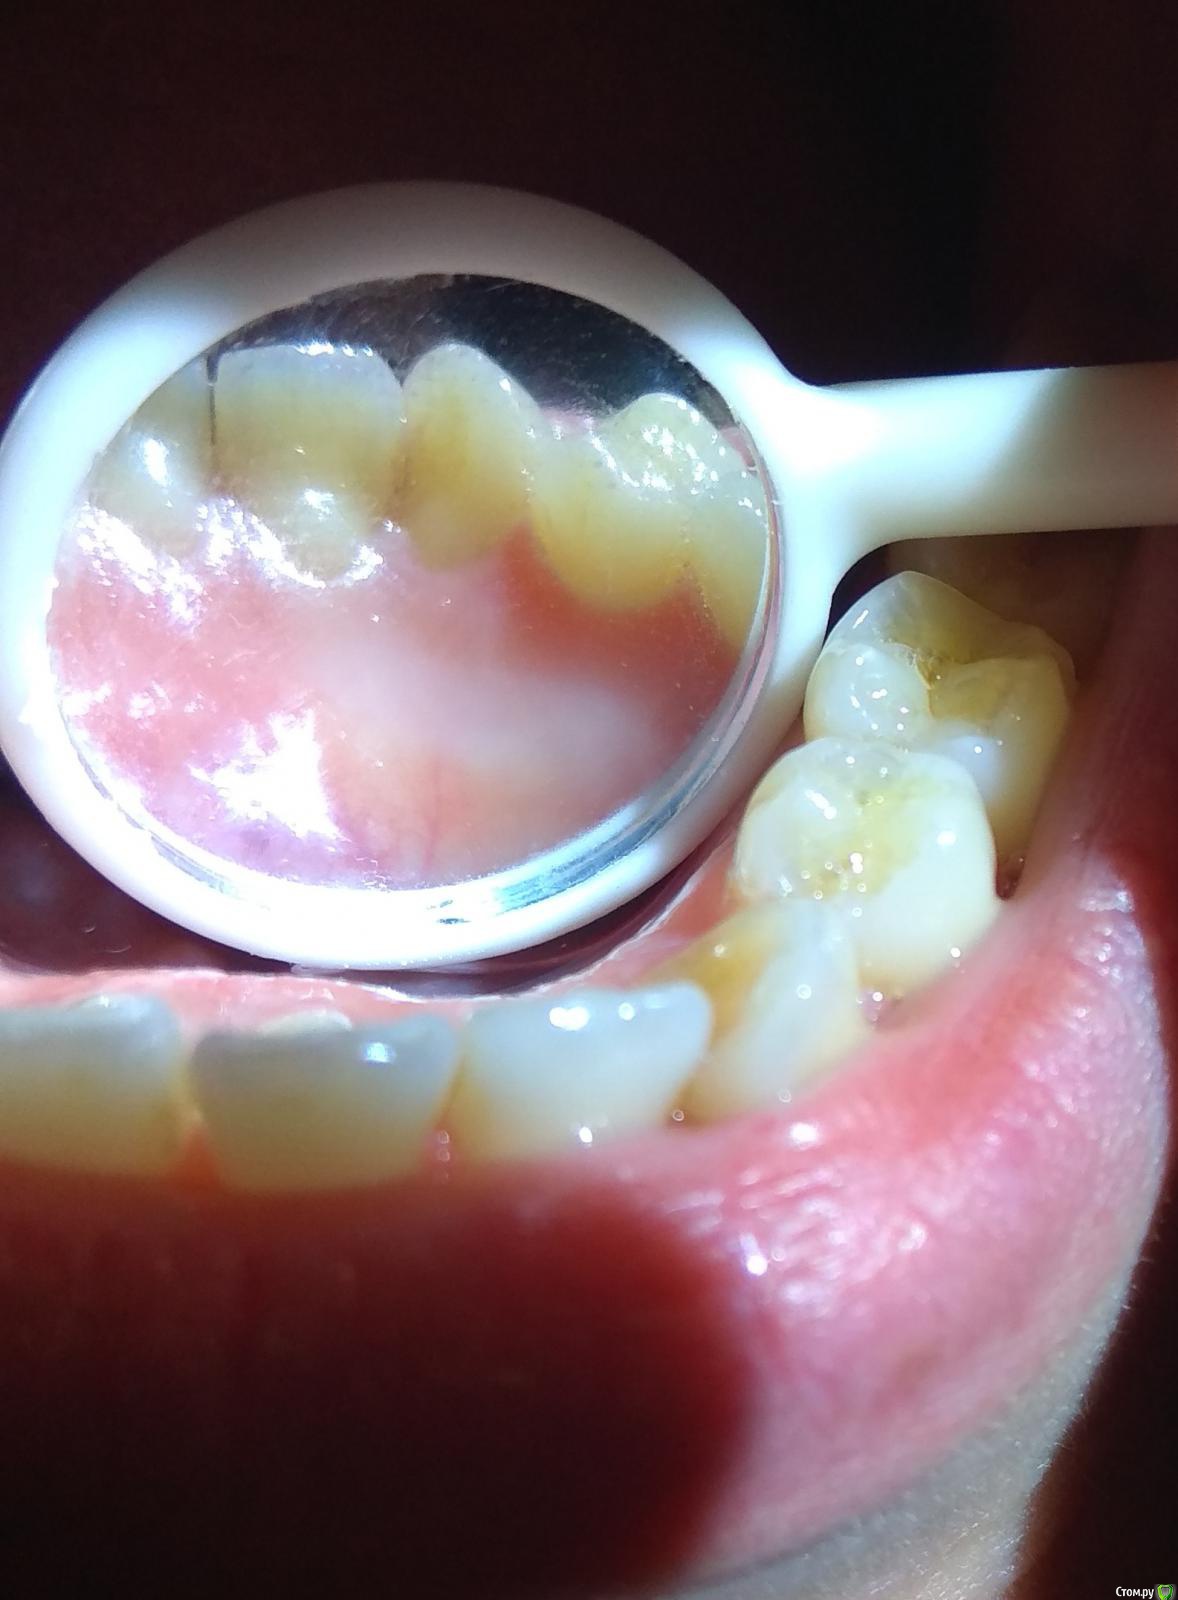

IAmValeria Опубликовано 13 апреля, 2020 Автор Поделиться Опубликовано 13 апреля, 2020 А как болят и где именно? Попробуйте описать максимально подробно.Например: от холодного-горячего болят или сами по себе или при жевании?Больше с утра, в середине дня, к вечеру или в разное время?Какая боль - остро стреляет, тянет, ноет, распирает? Между приступами боли совсем ничего не беспокоит или фоново что-то чувствуется?Боль куда-то отдает или четко локализована в одной точке?Что-то помогает снять боль или проходит сама?Принимали ли обезболивающие типа Ибупрофена или Нимесила? Помогает ли?Попробую описать. Боли начались с клыка слева, с той стороны, где удаляли зуб. Сразу после удаления, как только отошла анестезия. Через две недели после удаления было принято решение пролечить семёрку. Лечу я всегда в анестезией. После анестезии, ещё во время нее, в процессе заморозки, может, через 30 минут после укола началась дикая боль в клыке и рядом стоящих зубах. Сильнее, чем прежде. Боль такая, словно зуб очень чувствительный, когда бывает эмаль реагирует на сладкое, например. Только она не проходит. Словно включается по кнопке и так же выключается. Не пульсирует, не стреляет. Боль словно одной тональности. Иногда она невыносимая. Я бы не сказала, что она усиливается от горячего/холодного или во время приема пищи. Когда у меня ничего не болит, я спокойно ем и пью что горячее, что холодное. Во время приступа мне больно даже прикасаться к зубам на этой стороне. За день таких приступов может быть порядка 5-10. Некоторые проходят за 5-10 минут, некоторые длятся несколько часов. Обычно к вечеру боль и продолжительность усиливаются. Обычно я сплю хорошо, но два раза просыпалась от невыносимых приступов, которые длились около 10 минут. Боль сконцентрирована в клыке, потом она доходит до передних зубов и до 7 по той же стороне, что и клык (по левой), но самая сильная боль всегда в клыке и рядом стоящих с ним зубах. На всякий случай я прикрепляю и снимок клыка. И фото с обратной стороны тоже. Клык кривоват. Вообще, это снимок четверки, но и клык там есть. Когда у меня не приступ, в клыке и примыкающих зубах все равно неприятное ощущение, словно натруженности, но оно незначительное. Я пробовала пить пенталгин и пенталгин-H, иногда помогает, иногда нет. Зависимости нет. Пенталгин-H помогает лучше, чем пенталгин. Так же перед лечением семёрки врач 9 дней покрывал зубы фторлаком. Пожалуйста, помогите мне. Поймите, я не сумасшедшая, которая ищет советов в интернете и не хочет идти к врачу. Меня смотрели 4 опытных врача. К какому-то решению не пришли. Мне кажется иногда, что я схожу с ума от боли. Ссылка на комментарий

shishok Опубликовано 13 апреля, 2020 Поделиться Опубликовано 13 апреля, 2020 А в клыке пломба стоит? Ссылка на комментарий

St. Опубликовано 13 апреля, 2020 Поделиться Опубликовано 13 апреля, 2020 Ситуация и правда не стандартная... И то что Вы ищете решение - это абсолютно нормально, ничего плохого). Вариантов может быть несколько.1й воспалился нерв в клыке (по фото кажется в нем есть пломба, правильно?). Проверить проще у стоматолога специальным очень холодным спреем, но можно и дома, конечно не так точно, приложив маленькую ледышку к зубу. Решается относительно быстро лечением корневых каналов. Но смущает время появления боли.. Хотя совпадения пусть и редко, но тоже встречаются.2й во время удаления зуба мудрости травмировался нерв, так бывает когда корни зуба находятся совсем рядом с нервом. Решается уже сложнее дольше. Подтверждается исключением проблем с зубами. Ссылка на комментарий

IAmValeria Опубликовано 13 апреля, 2020 Автор Поделиться Опубликовано 13 апреля, 2020 А в клыке пломба стоит?Нет, в клыке пломбы нет, может, так кажется, потому что он кривоват и как бы заходит за другой зуб? Ссылка на комментарий